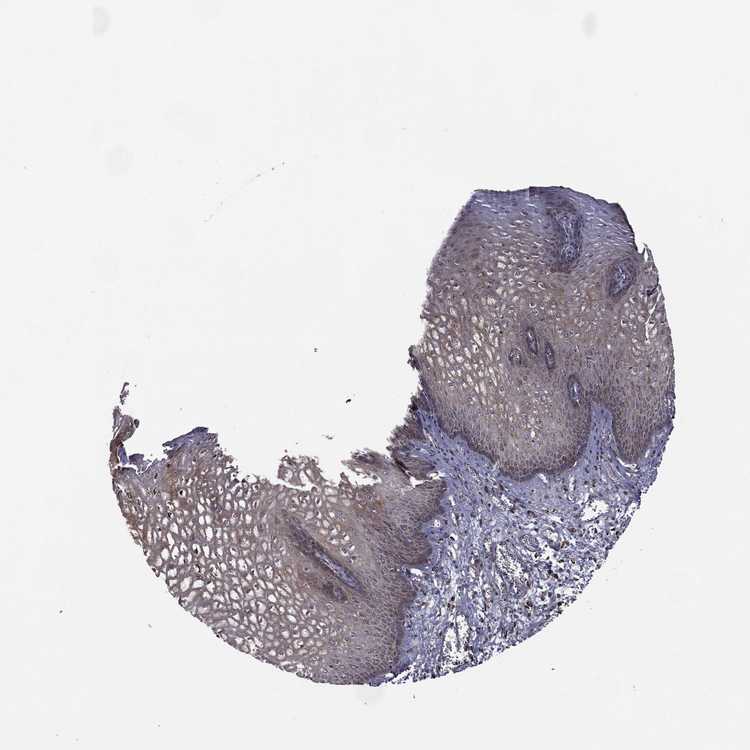

ESOPHAGUS - Antibody stainingi

Antibody staining in the annotated cell types in the current human tissue is reported as not detected, low, medium, or high, based on conventional immunohistochemistry profiling in selected tissues. This score is based on the combination of the staining intensity and fraction of stained cells.

Each image is clickable and will lead to virtual microscopy that enables deeper exploration of all samples and also displays staining intensity scores, fraction scores and subcellular localization as well as patient and tissue information for each sample.

Antibody HPA058824

Squamous epithelial cells Medium